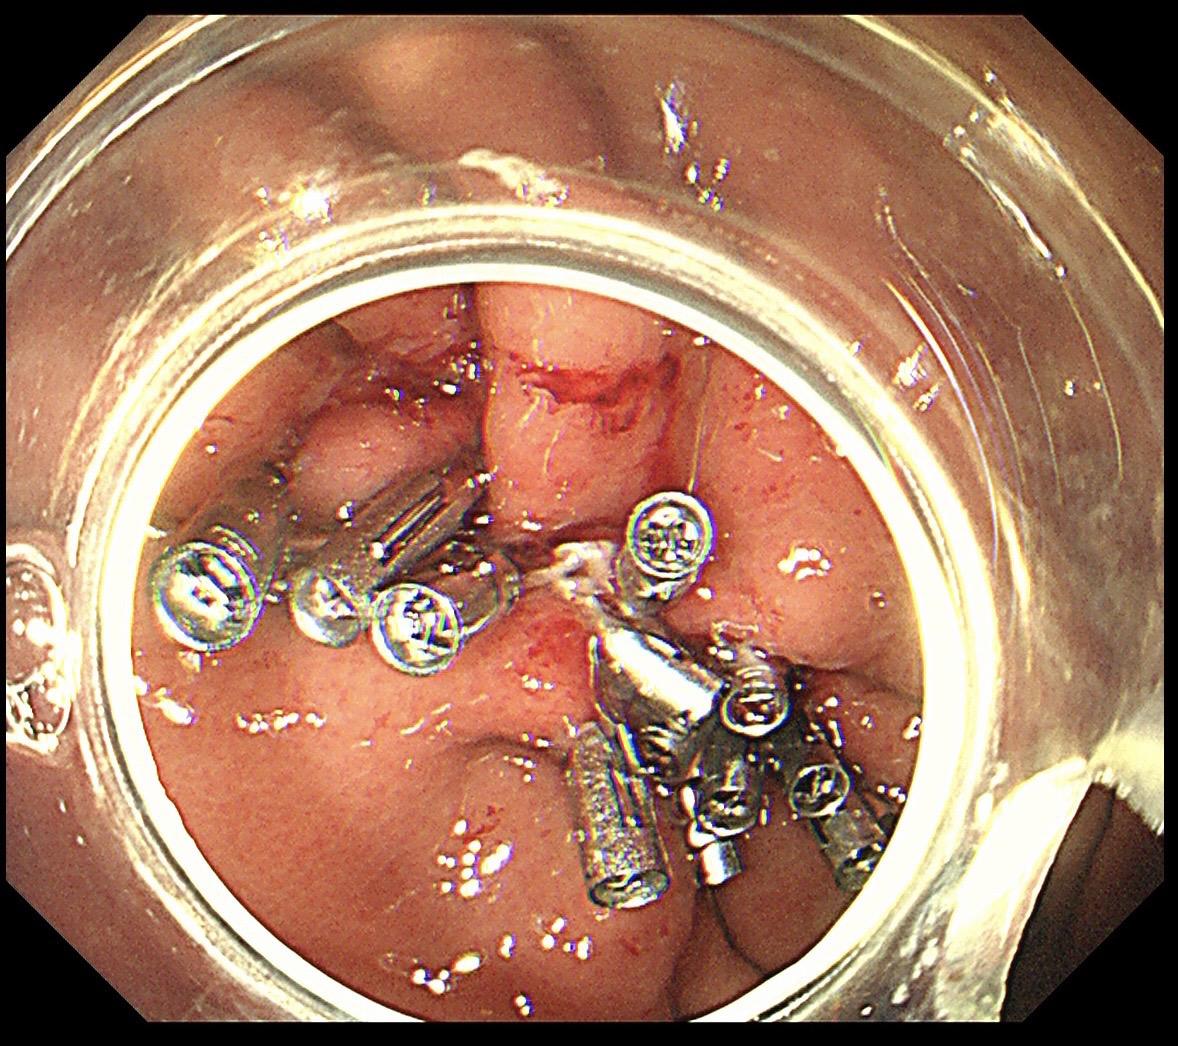

胃黏膜下隆起都是间质瘤吗?不是的!这个很像间质瘤的胃黏膜下隆起,其实是胃壁钙化的结核结节!切胃黏膜下隆起就像开盲盒,病理没出来谁也无法完全确定!